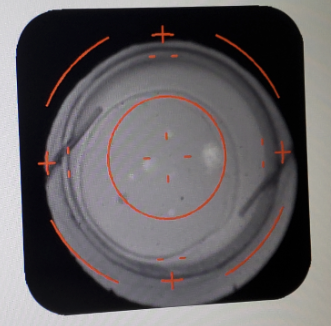

Image credit: Bryan S. Lee, MD, JD.